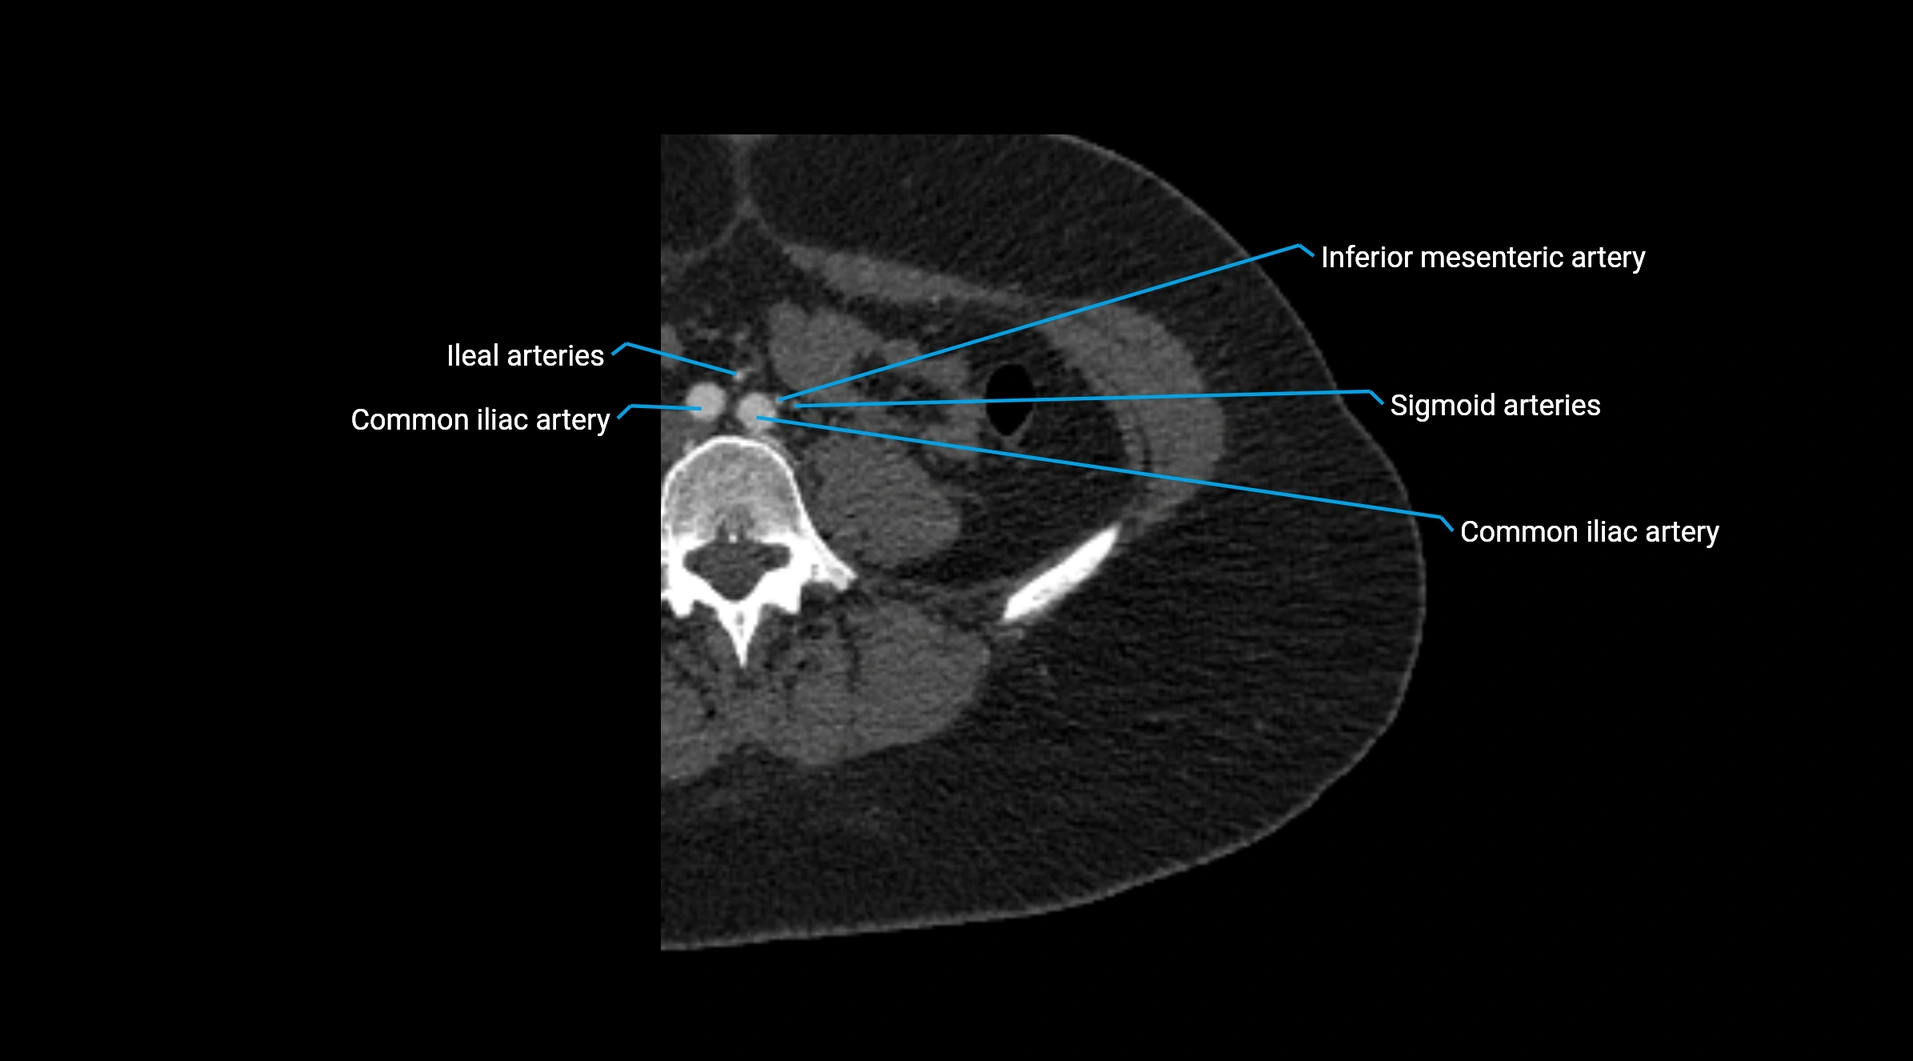

• Unpaired visceral branches: celiac trunk, superior mesenteric artery (SMA), inferior mesenteric artery (IMA)

• Terminal branches: right and left common iliac arteries

Contrast-enhanced CT (CTA):

• Gold standard for abdominal aortic imaging

• Provides excellent detail of lumen, wall, aneurysm, thrombus, and branch vessels

• Multiplanar and 3D reconstructions help in aneurysm measurement, stent graft planning, and dissection evaluation